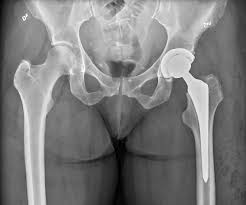

Kalça protezi sonrası fizyoterapi

İleri yaşta, genellikle düşme sonrası kırıkların ted.